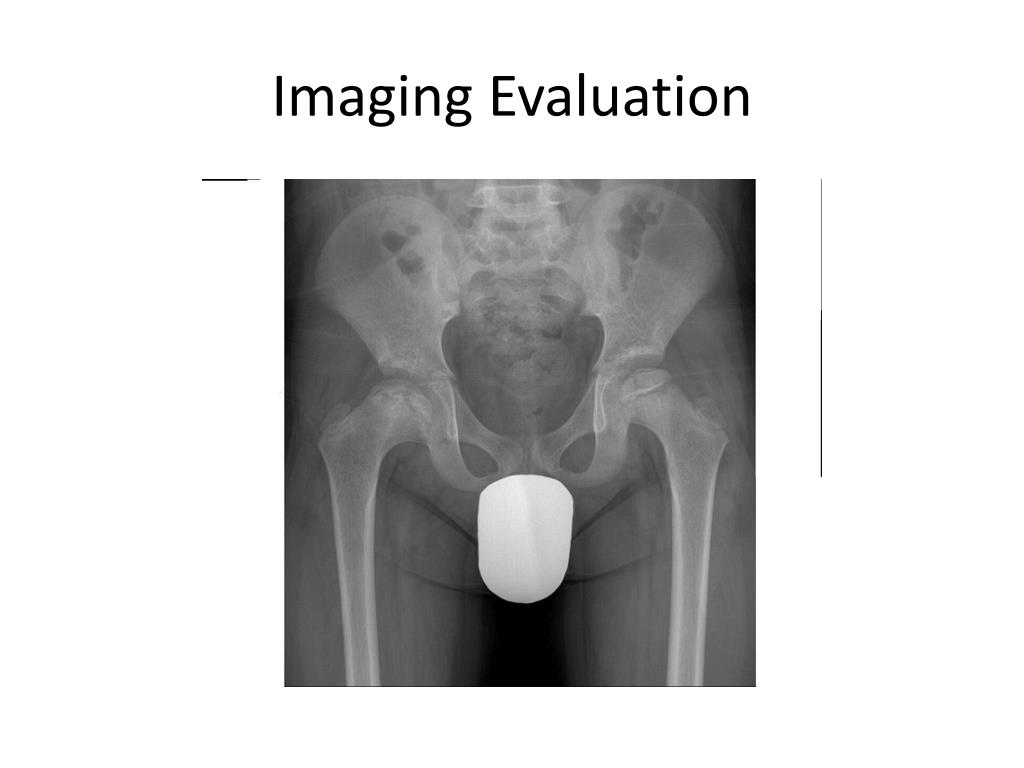

15. Imaging Evaluation

16. Imaging Evaluation

18. Imaging Evaluation • MRI • Bone scan • Arthrography • X-ray